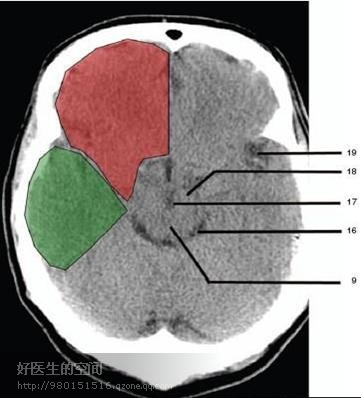

16、环池 (Ambient cistern) 17、角间池 (Interpeduncular cistern) 18、大脑角 (Cerebral peduncle) 19、侧裂池 (Sylvian fissure) 绿色部分为颞叶(Temporal Lobe),浅红色部分为额叶(Frontal Lobe)